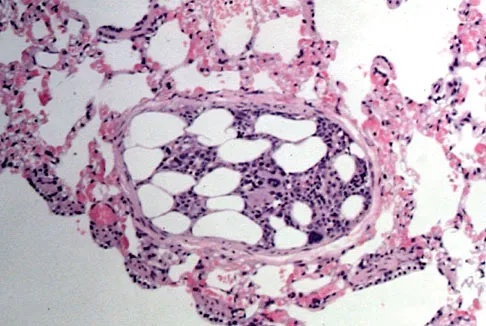

Embolic material generated during total knee arthroplasty (TKA) shown in Figure 29 is composed of which of the following substances?

Explanation